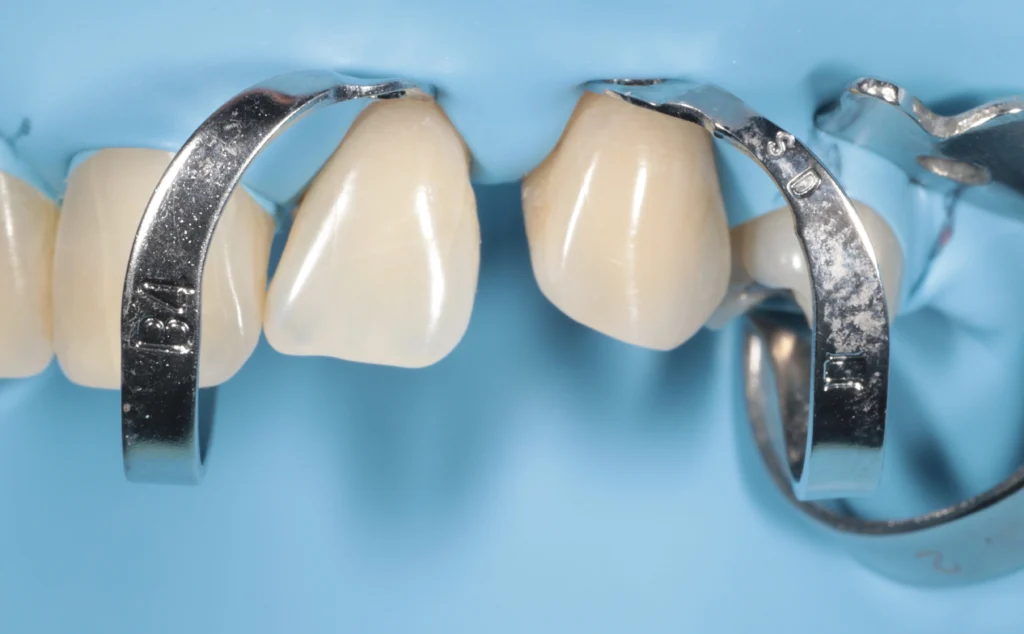

Composite Bonding in Beirut

A simple, fast, and natural solution to improve your smile in one visit.

Composite bonding is a minimally invasive cosmetic treatment used to repair chipped teeth, close gaps, and improve shape and color. Using high-quality materials and precise techniques, we can restore your teeth in a single session with results that blend seamlessly with your natural smile.